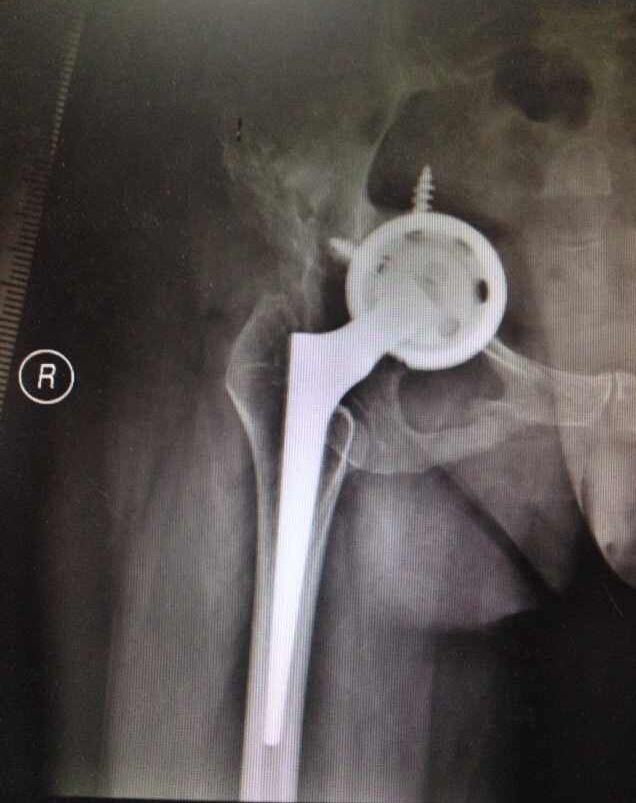

女46,髋关节置换术后假体松动骨缺损